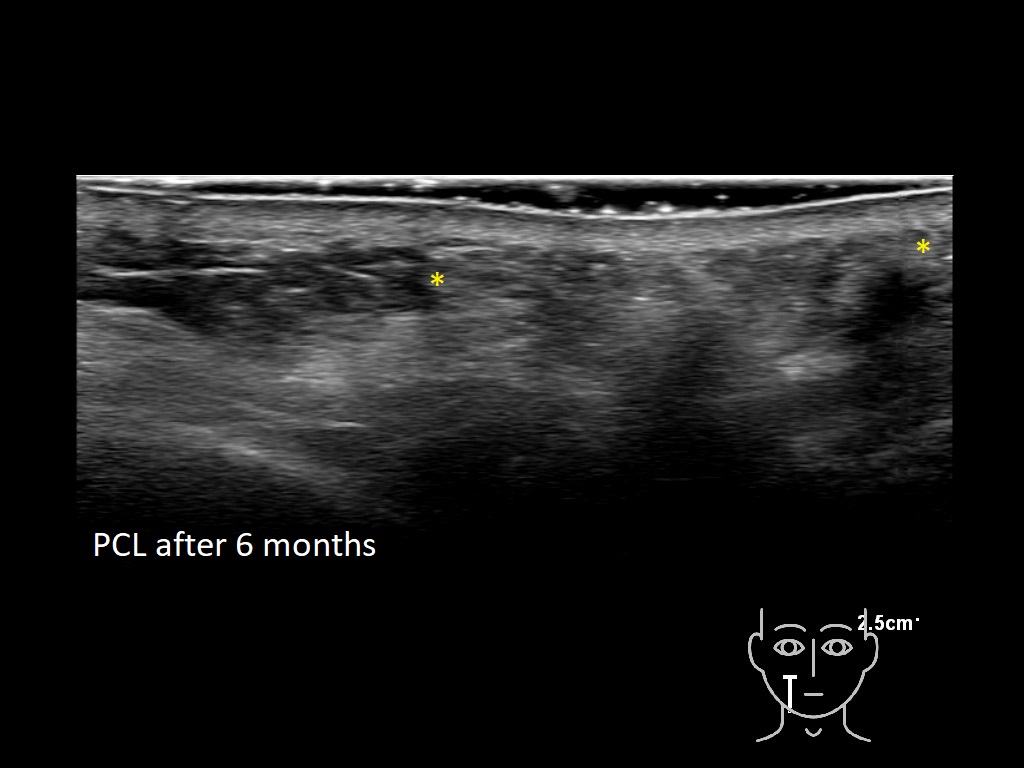

Draw in the second image below where the fillers are located. To check if your answer is correct, swipe the first image to the right.